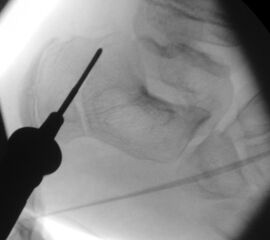

=> Risikoabwägung der radiologisch leicht erhöhten Strahlenbelastung intraoperativ

In der minimalinvasiven Fußchirurgie ist es unabdingbar, die Fräse in ihrer Position zum Knochen radiologisch zu kontrollieren, damit vulnerable Wachstumsfugen oder angrenzende Gelenke nicht verletzt werden. Zu diesem Zweck werden mit einem Bildwandler während der Operation die genaue Position der Fräse und der Osteotomieverlauf überprüft, was die Strahlenbelastung im Vergleich zu offenen Verfahren erhöht. Diese Strahlenbelastung hat potenziell einen schädigenden Einfluss auf den noch blutbildenden Knochen von Heranwachsenden. Gesicherte Landmarken am Fuß können die notwendige Zahl der Röntgenbilder und damit die Strahlung minimieren. Ist es erforderlich, mehrere Knochen zu osteotomieren, wie zum Beispiel im Bereich der Kleinzehen, werden anhand der Landmarken kleine Injektionsnadeln auf Höhe der geplanten Osteotomien vorgelegt und radiologisch im Bildwandler (BV) dokumentiert (Abb. 11). Ein solches Bild schafft eine gute Orientierung, sodass auf radiologische Kontrollen intraoperativ weitestgehend verzichtet werden kann.

Abb. 11: Lokalisation mehrerer Stichinzisionen mit einem Röntgenbild.

Zum Lesen der Bildbeschreibung und zur Vollansicht bitte das Bild anklicken. Bild: A. Helmers.